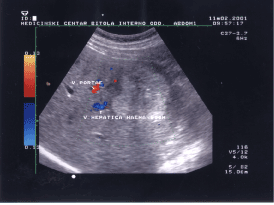

The color Doppler ultrasound image presented by figure 1 showed hepatocelular carcinoma (HCC) complicated with hepatic cirrhosis (autopsy proven), with emboli in the portal vein detected previously by conventional B-mode ultrasonography. The rounded lesion with hypoechoic “halo” largest in diameter and localized in the left part of the image presented as HCC. The smaller hypoechoic lesions are secondary metastatic deposits. Color Doppler arbitrarily displays blood flow toward the transducer as red and it is generated by portal vein blood flow. The blood flow away from the transducer as blue and it is belonging to hepatic vein flow. Sometimes, we used the terms antegrade and retrograde to describe flow in this context. At spectral Doppler blood flow (angiodinogram) toward the transducer is displayed above the baseline (antegrade flow) and blood flow away from the transducer is displayed below the baseline (retrograde flow) [7]. The branch of hepatic vein presented as blue vessel in 8-9 a clock position, superficially incorporated in HCC is the feeding vessel. The small red colored crescent area in 2 a clock position is presented by hepatic artery.

Figure 1. Image of iso/hypoechoic round, heterogeneous and moderately well-defined lesion showing the vessel that feeds the lesion (hepatocelular carcinoma).